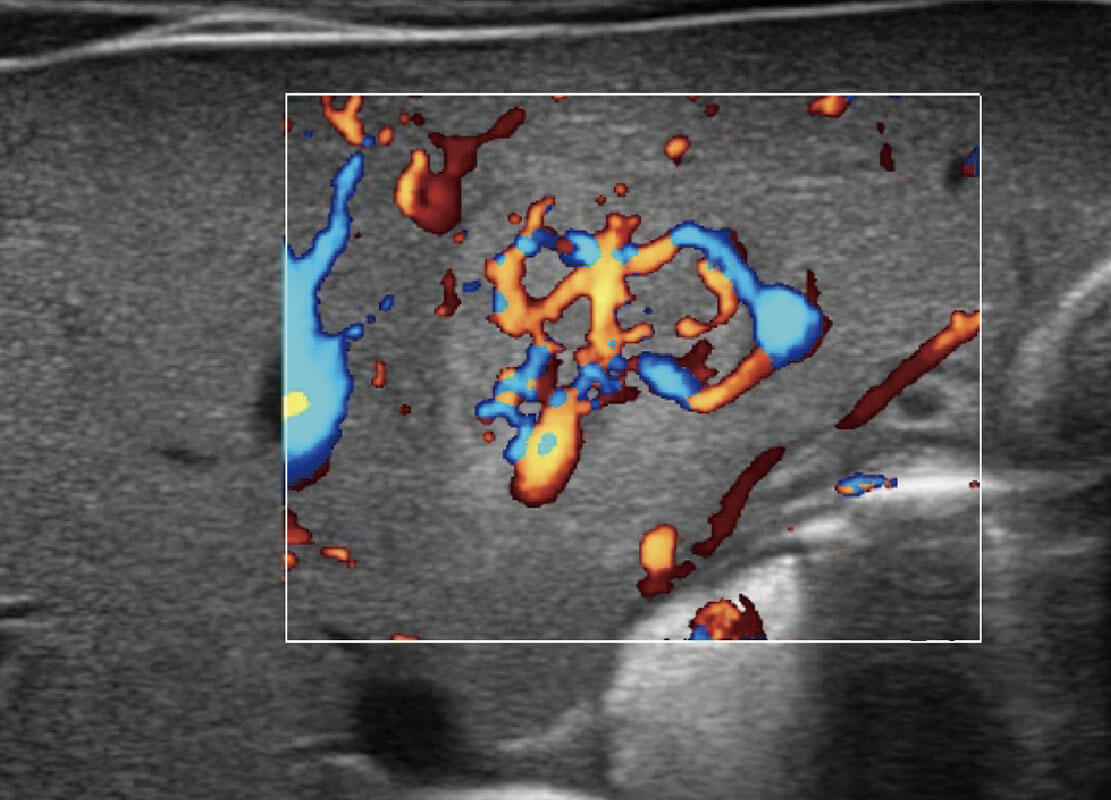

P60优异的图像质量搭载专科探头,在妇科基础疾病的诊断、卵泡生长的监测、输卵管通畅情况的判别等方面为您提供生殖应用方案。

腔内妇科-宫腔分离

腔内妇科-卵巢

腔内三维-宫内节育器

腔内三维-光影成像